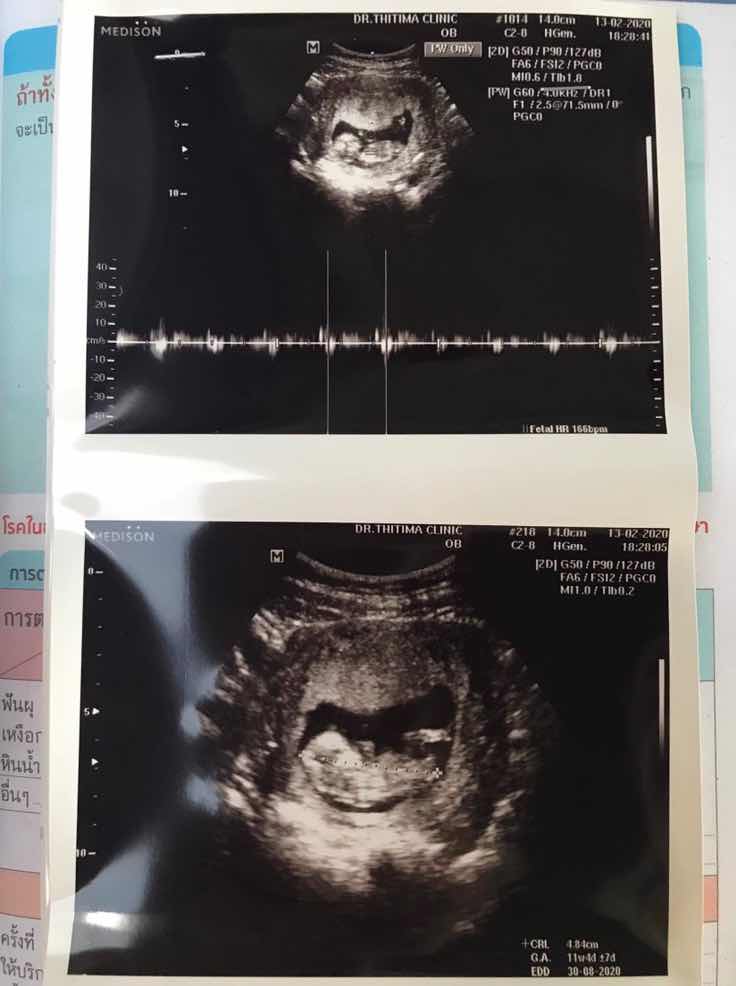

11wค่ะ

Post reply image